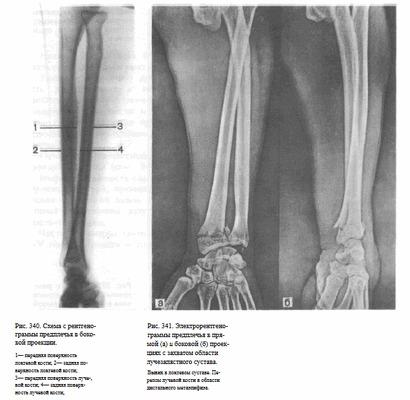

Укладка больного для выполнения снимка. Больной сидит боком к столу.

Рука отведена, расположена на столе или на подставках. Кассета размером 18X24 или 24X30 см, наполовину перекрытая листом просвинцованной резины, располагается под задней поверхностью предплечья таким образом, чтобы на снимке были захвачены проксимальные и дистальные концы костей. Пучок рентгеновского излучения направляют на середину предплечья перпендикулярно кассете. Фокусное расстояние — 100 см (рис. 337).

Информативность снимка. На снимке видны диафизы и метаэпифизы лучевой и локтевой костей, их медиальные и латеральные поверхности, мозговые полости и корковое вещество (рис. 338).

Критерии правильности укладки. На прямом заднем снимке изображения костей предплечья не должны наслаиваться друг на друга. Обязательно должны быть отображены либо дистальные, либо проксимальные метаэпифизы костей, без чего невозможна правильная ориентация снимка.

СНИМОК ПРЕДПЛЕЧЬЯ В БОКОВОЙ ПРОЕКЦИИ

Назначение снимка. Снимок чаще всего выполняют при травме в сочетании со снимком в прямой задней проекции.

Предплечье и кисть прилежат к столу ульнарной поверхностью. Положение кассеты и центрация пучка рентгеновского излучения такие же, как при выполнении прямого заднего снимка предплечья (рис. 339).

Информативность снимка. На снимке видны диафизы и метаэпифизы обеих костей предплечья, корковое вещество и мозговые полости костей (рис.340, 341).